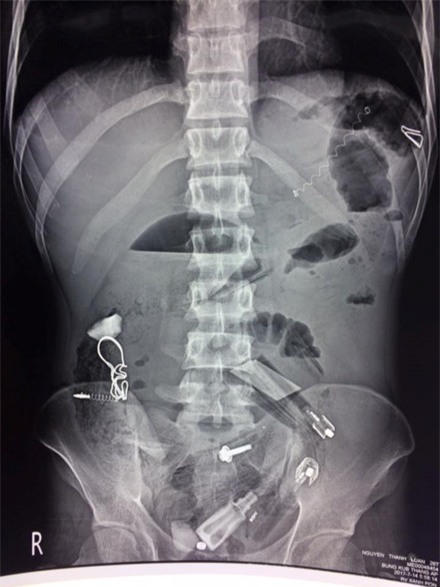

Các bác sĩ chụp X-quang và phát hiện rất nhiều dị vật trong cơ thể bệnh nhân.

Trước đó, sáng 15/7, bệnh viên tiếp nhận bệnh nhân có biểu hiện chướng bụng, mê sảng. Kết quả chụp X-quang cho thấy, trong dạ dày bệnh nhân có rất nhiều dị vật nên chỉ định phẫu thuật. Trong quá trình thực hiện, các bác sĩ đã lấy ra rất nhiều dị vật như bật lửa, lò xo bút bi, bút bi, thìa nhựa, lá cây, vỏ kẹo, vỏ thuốc, đinh…, tổng cộng hơn 30 dị vật.